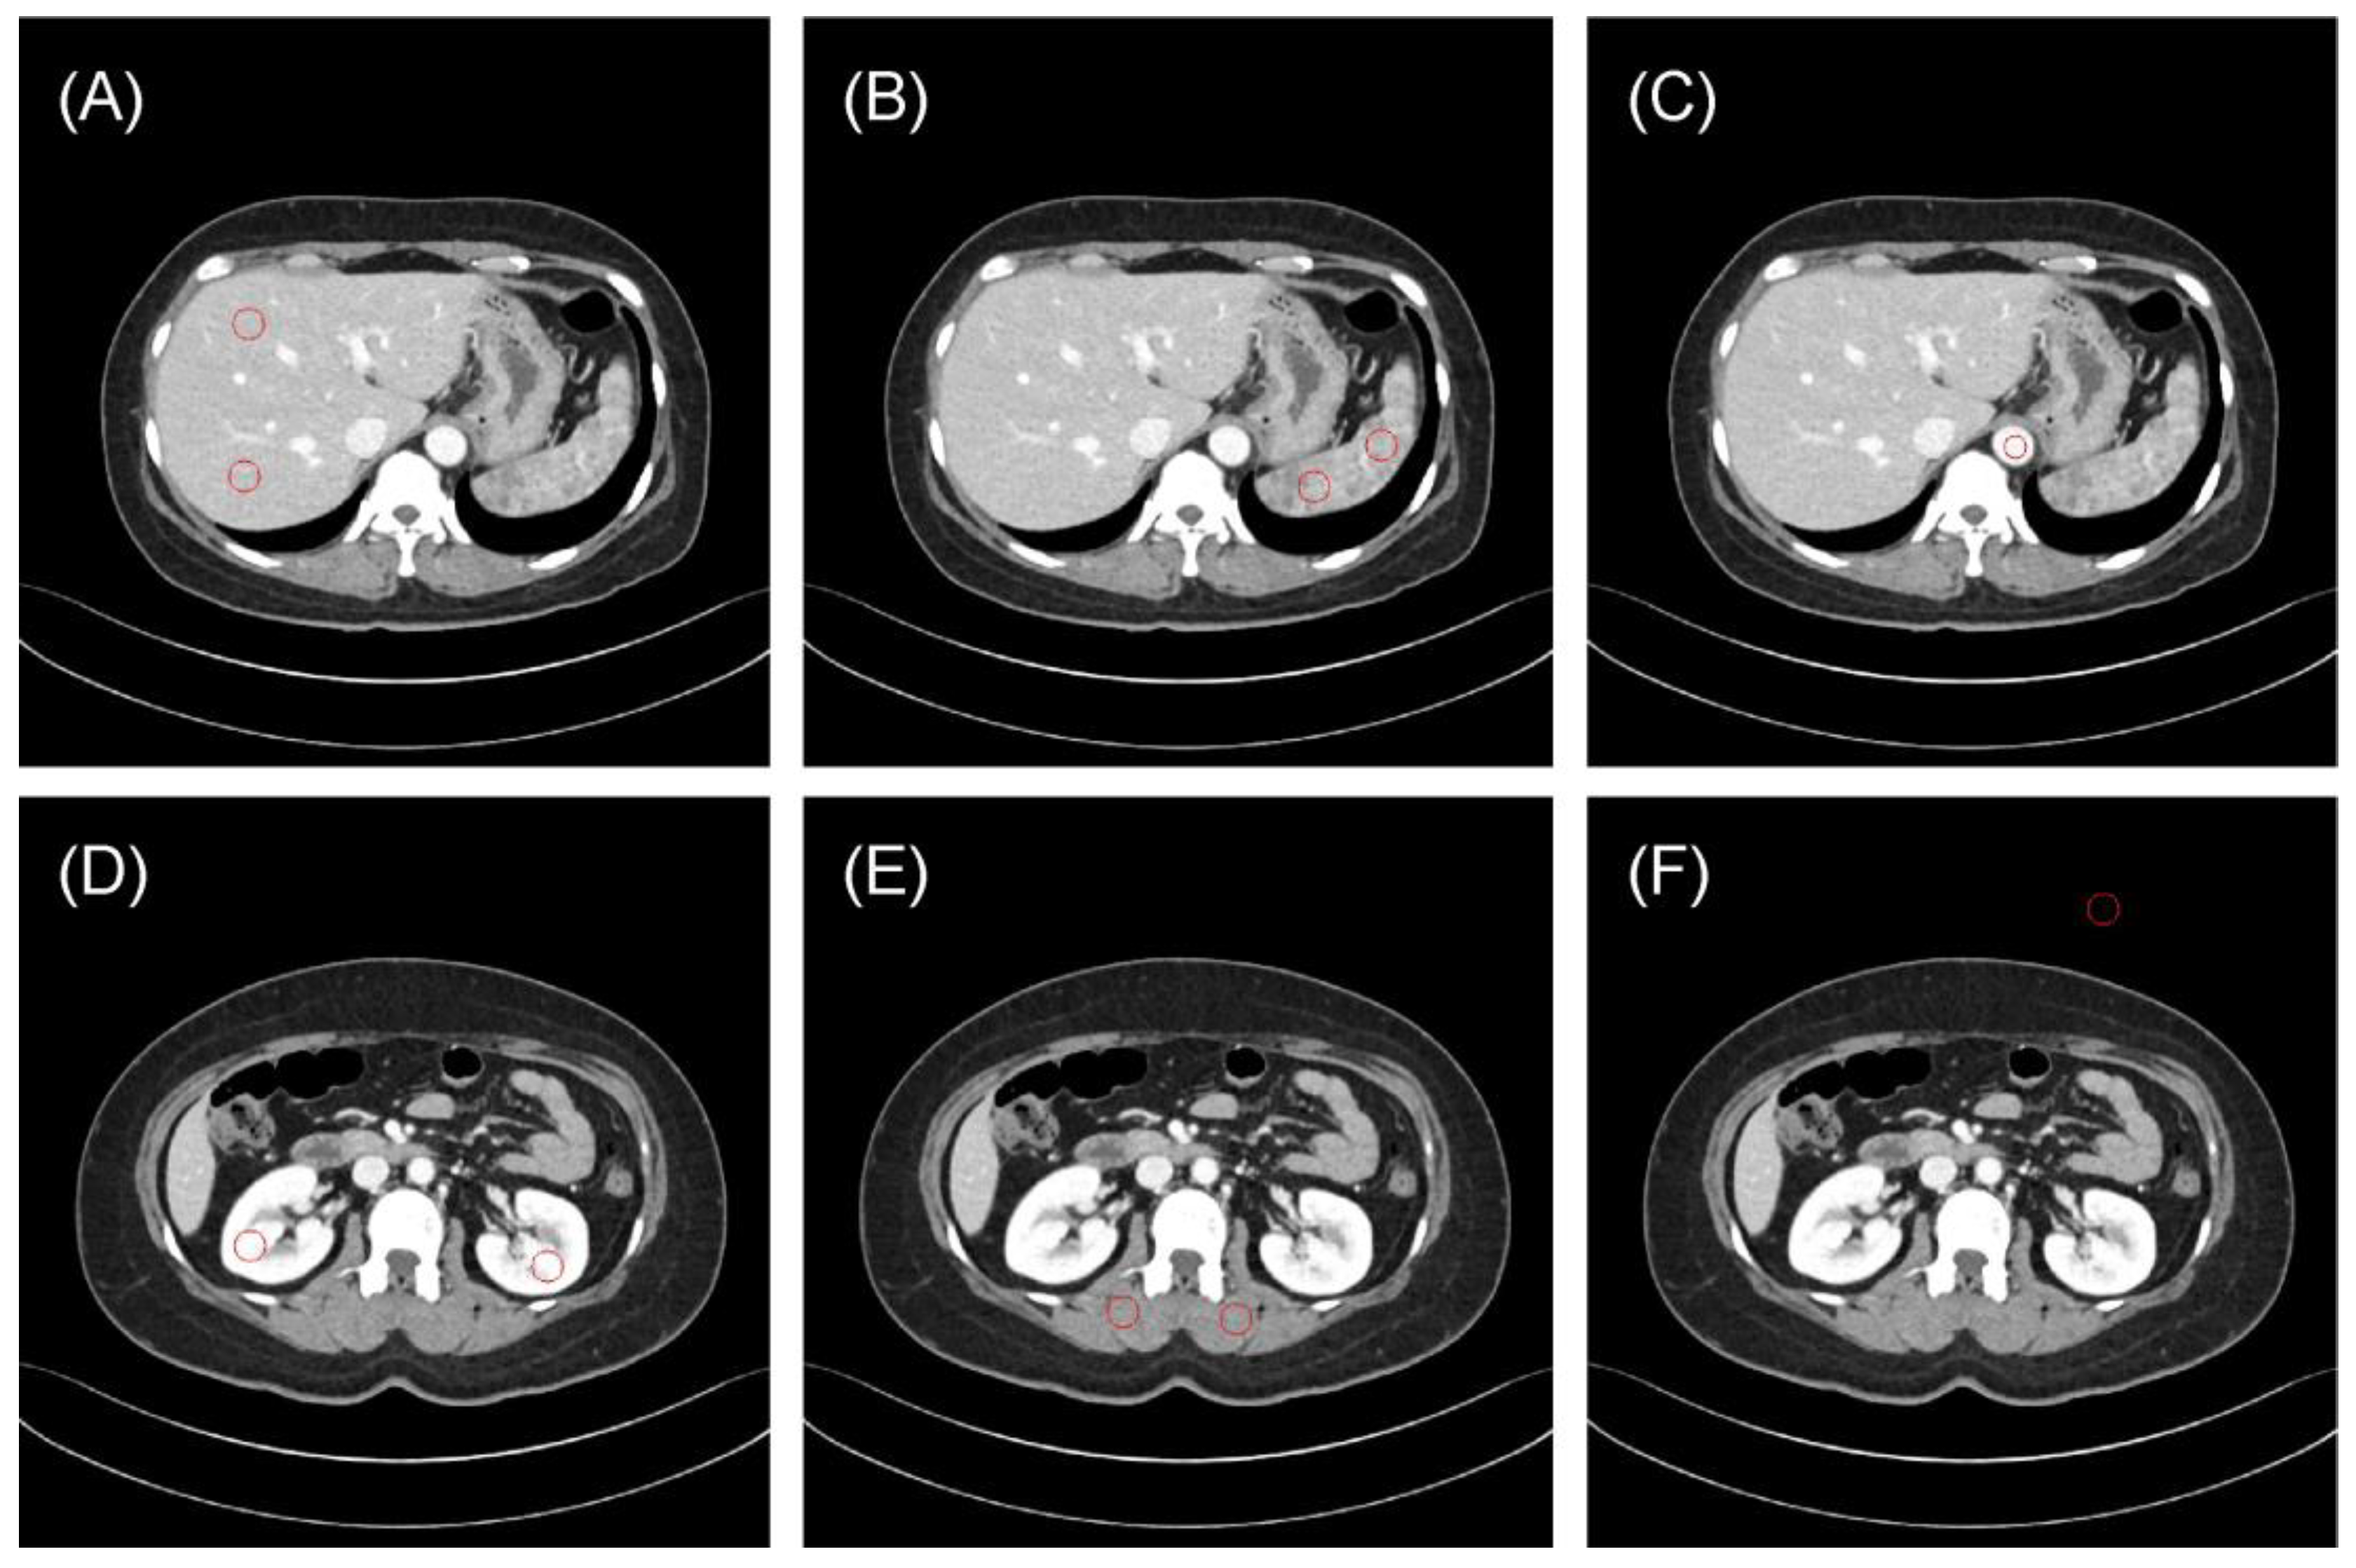

3.1. Region-Based Reproducibility Analysis

3.2. Patient-Based Reproducibility Analysis